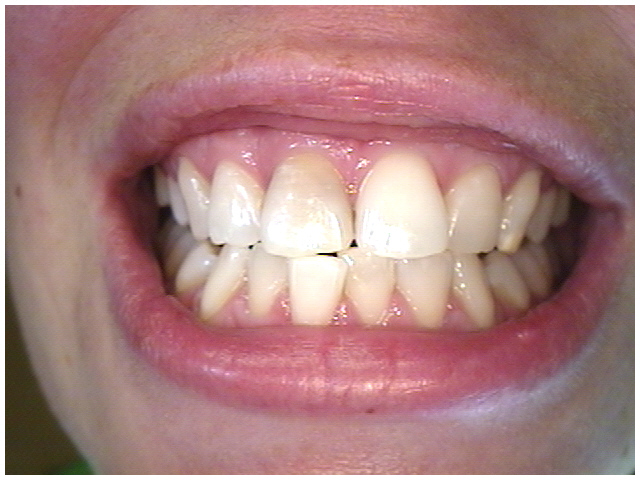

When the nerve inside your tooth becomes non-vital(dead) the tooth often undergoes a colour change. This is very noticeable when the tooth is a front tooth. Normal teeth whitening applied from the outside(as in tray whitening) will not have a noticeable effect.

Dark front tooth

Dark front tooth indicating

the tooth is 'dead'